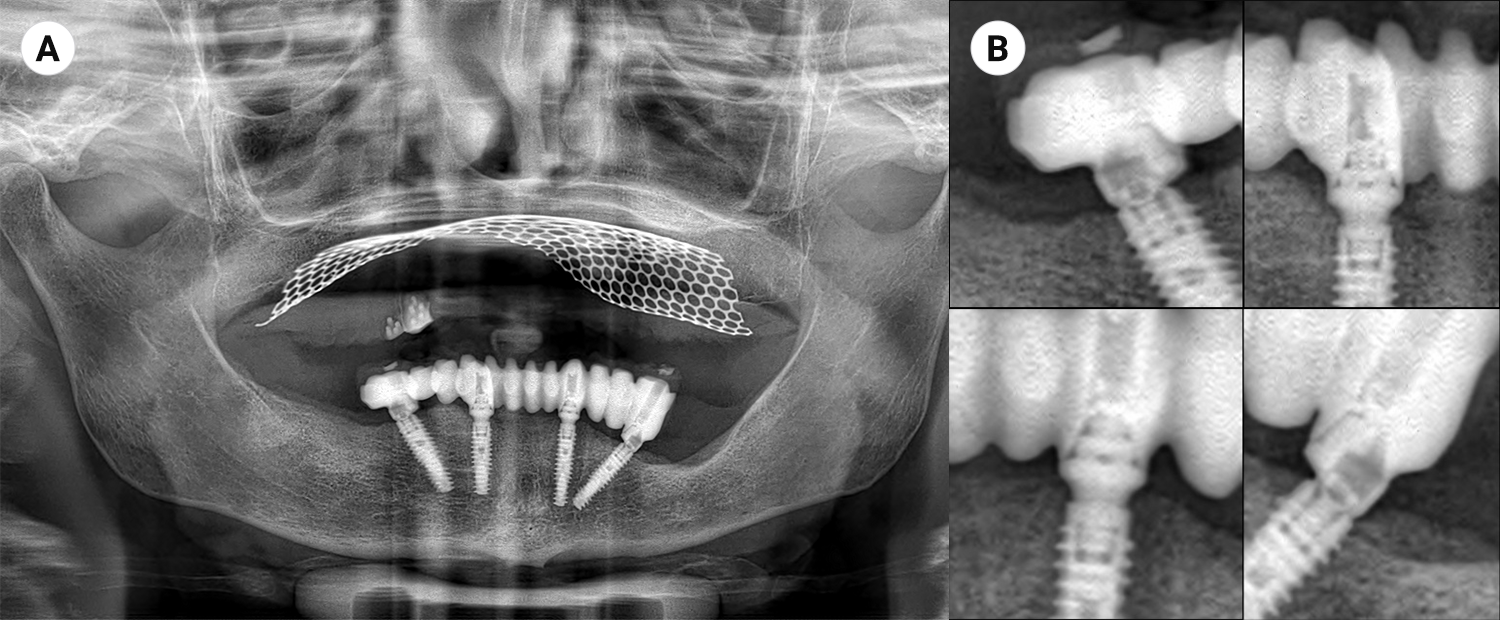

Un altro importante vantaggio di questo protocollo 100% digitale, è che la protesi realizzata in flusso CAD/CAM risulta sempre passiva sui MUA implantari, grazie alla accuratezza delle scansioni pre e intra operatorie. La protesi, inoltre, è dotata di una rigida sottostruttura in titanio monoblocco che garantisce il necessario splintaggio ortopedico, che numerosi studi di letteratura indicano come necessario per poter raggiungere con maggiore predicibilità l’osteo integrazione degli impianti (Fig.12).

Opt al tempo 0

Fig. 12. (a) Opt al tempo 0, che evidenzia la sottostruttura in titanio con connessioni implantari parti integranti della stessa; (b) Particolari ingranditi delle connessioni implantari che si presentano passive con la sottostruttura della protesi.